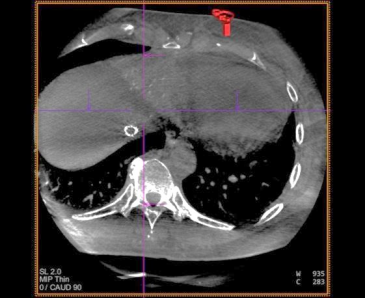

术中 CBCT 可见肝左内叶肿瘤强化病灶

CBCT 扫描血管重建可见,血管迂曲及靶病灶大小和位置

栓塞结束后 CBCT 扫描,原肝左内叶病灶无强化